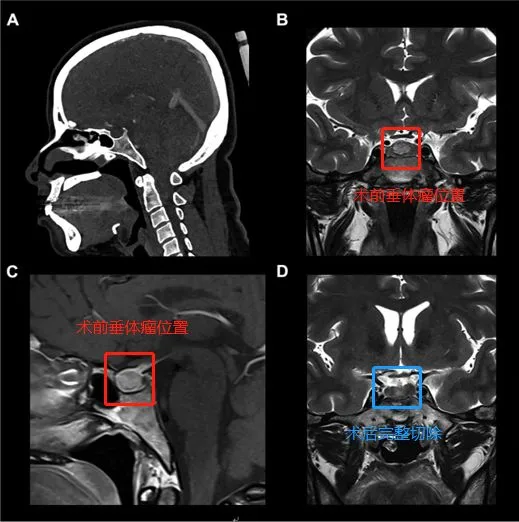

一名37岁的女性接受了促肾上腺皮质激素分泌型微腺瘤(库欣病)的手术。术前磁共振成像(MRI)显示位于蝶鞍中央的9mm微腺瘤(图4A)和(图4C)并且计算机断层扫描仪显示了蝶窦的鞍周型气管化(图4B)。在右中鼻甲侧化后,通过右侧单侧使用筷子手法进行广泛的蝶窦切开术。筷子手法有助于从手术区域清除血液并解剖假包膜平面,进而完整地整块切除肿瘤(不分块切除,防止肿瘤残留)。从最终的术后影像学上来看,肿瘤是被肉眼下完整切除的(图4D),并完成内分泌治疗。